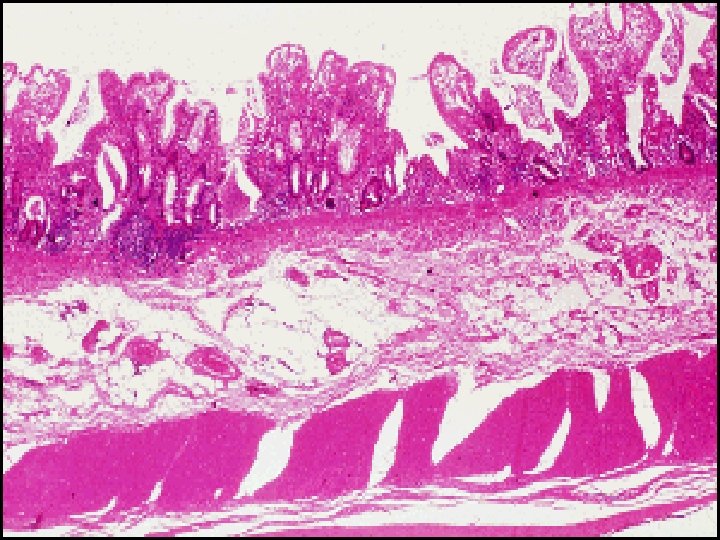

Histopathology of IBDS v. Ulcerative Colitis: -- The inflammatory process is limited to the mucosa . Acute & chronic inflammatory cells infiltrate the lamina propria & crypts ( Cryptitis ). Crypt abscesses are typical. -- Distorted Goblet cell which loss its mucus. -- Dysplasia : increased mitotic rate + nuclear atypia which herald the development of Ca colon.

v. Crohn , s disease: --The whole wall of the intestine is oedematous & thickened , There are deep ulcers which appear as linear fissures with normal mucosa between them ( cobblestone). -- Fistulae & ulcers. -- The lesion is patchy ( skip lesion ). -- Chronic inflammatory cell infiltrate the whole layers -- Microgranuloma (aggregate of histeocytes which surrounded by lymphocytes & contain giant cells). -- Aphthus ulcer.